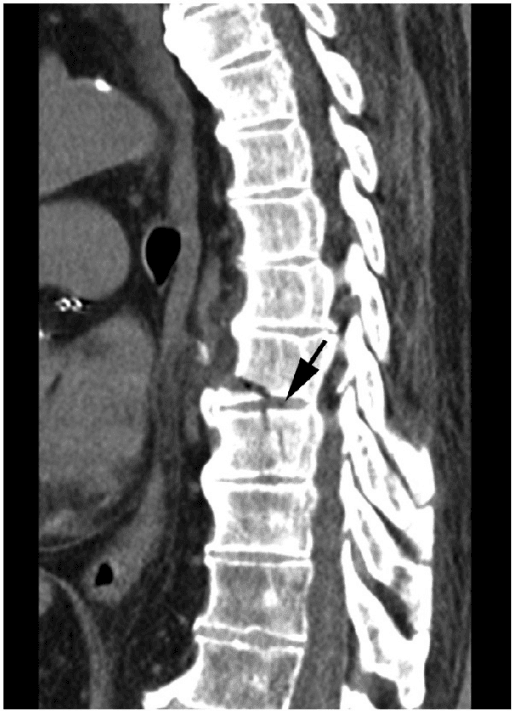

4. Endplate Fracture

An endplate fracture is a break in the bony endplate of a vertebra. In the context of ACDF, it can occur during the surgical procedure, especially when preparing the vertebral endplates for the placement of a bone graft or cage. This fracture can be caused by:

- Over-preparation: Excessively removing the endplate during surgery can weaken the bone, making it more prone to fracture. The aim of endplate preparation is to expose the vascular cancellous bone to promote fusion, but removing too much of the hard cortical bone can increase the risk of the cage or graft sinking into the vertebral body, a complication called "subsidence."

- Screw Penetration: Driving a screw too close to or through the endplate can cause a fracture.

- Pre-existing conditions: Patient factors can elevate the risk of endplate fracture. Osteoporosis, for example, weakens the bone, making it more fragile and prone to breakage fracture.

An endplate fracture can lead to several complications, including:

- Subsidence: This is the most common and significant consequence. Subsidence occurs when the cage or graft sinks into the softer cancellous bone of the vertebral body. This can lead to a loss of disc height, changes in spinal alignment (kyphosis), and potential nerve root compression.

- Non-union (pseudarthrosis): If the endplate is severely damaged, it can hinder the fusion process. The lack of a stable base for the graft can prevent new bone from growing, leading to a "failed fusion."

- Instability: A damaged endplate can compromise the stability of the surgical segment, potentially leading to the loosening or dislodgement of plates and screws.